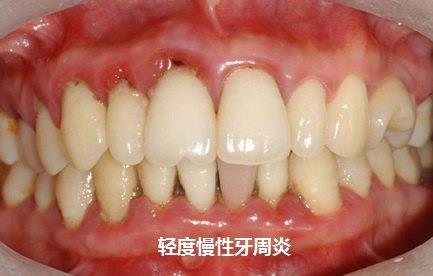

在現(xiàn)實生活中有些人不僅存在著牙齒畸形的問題,還伴隨著牙周病,牙周病是導(dǎo)致牙齒脫落的重要因素,牙周病的出現(xiàn)嚴重影響到我們口腔的健康,在這種情況下想做牙齒正畸可以嗎?

什么情況下?lián)Q牙周炎可以做牙齒矯正呢?

一,牙周病必須已經(jīng)得到良好的控制穩(wěn)定至少在半年以上,牙周病變的靜止期才可以接受正畸治療。

二,牙周的狀況必須是在可以接受的范圍之內(nèi),牙槽骨的吸收量不能超過牙根正常長度的一半,更不能有正在發(fā)生的進行性吸收,牙齒不能有明顯的松動,牙齦的狀況要良好,沒有過度的增生和炎癥。

如果患者符合以上的條件,是可以進行正畸治療的,也就是矯正,但是在正常的治療過程中還是要密切監(jiān)控牙周狀況,嚴格控制口腔衛(wèi)生,隨時聽取牙周醫(yī)生的建議,總之牙周病患者是可以接受正畸治療的,但是需要承擔(dān)的風(fēng)險要比普通的患者大得多。